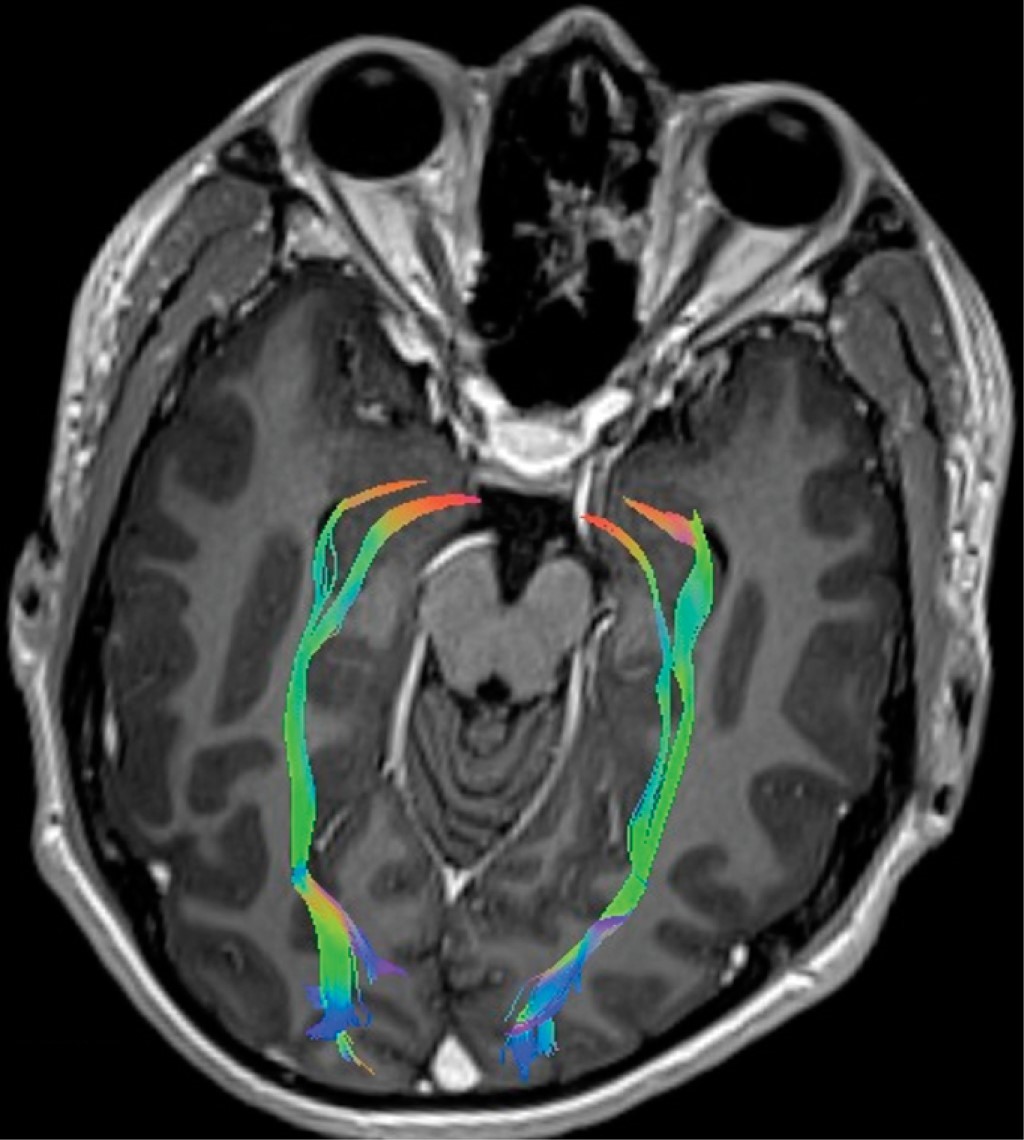

Paciente 1, 12 años, masculino, los valores obtenidos de FA fueron 0.000677609 (Figura 1) y de ADC 0.00647864.

La FA tiene un rango de 0 a 1, cuanto más cercano sea el valor numérico de este índice a 1, indicará que el tracto en estudio presenta preferencia por el movimiento o difusión en una dirección, secundario a la integridad de la capa de mielina que lo rodea (valor alto de FA), cuanto más cerca esté el valor de 0 (valor bajo de FA), reflejará una pérdida de la dirección preferencial, probablemente debido a una pérdida focal o difusa de la vaina de mielina.4 La fracción anisotrópica fue menor que los valores de control en nuestros tres pacientes, en el paciente 1 el resultado fue 0.000677609, en el paciente 2 fue 0.000525248, y en el paciente 3 fue 0.000104941, lo que refleja la presencia de desmielinización y daño axonal. Esto demuestra relación en cuanto a la base fisiopatológica de la enfermedad, donde la respuesta inmune provoca pérdida de mielina del nervio óptico y manifestaciones clínicas relacionadas con la neuritis óptica mediada o no por neuromielitis óptica o anticuerpos antiacuaporina, lo cual es interesante porque se inicia en la búsqueda definitiva, no sólo como cambios en las vías visuales sino también en un seguimiento a largo plazo, como un estudio que nos permita definir la severidad de la enfermedad y la respuesta a los tratamientos. En ese sentido el uso de la tractografía, especialmente en enfermedades neurológicas como la epilepsia y los tumores, ha abierto un camino más claro y novedoso en la evaluación de imágenes cerebrales, que ahora no sólo se limitan al conocimiento de las estructuras y su integridad, sino también al estudio de las vías y sus tractos.

En cuanto al ADC, éste nos habla de la difusión que existe entre las moléculas de agua con el tejido que la rodea a nivel extracelular. En nuestros tres pacientes los resultados obtenidos fueron inferiores en relación con el control (paciente 1: 0.00647864; paciente 2: 0.0200861; paciente 3: 0.0198284), estos hallazgos se observan cuando se produce un daño en el epineuro, dando como resultado un trastono en la difusibilidad, al entender que el epineuro es la capa nerviosa que puede sufrir un daño más inmediato ante procesos inflamatorios de diversas etiologías.4

En conclusión, los hallazgos en FA y ADC del nervio óptico podrían ser predictores del curso de la enfermedad; sin embargo, para establecer este hecho es necesaria una cohorte de pacientes con la enfermedad; por lo tanto, este estudio piloto abre la perspectiva. Es interesante observar en las imágenes por tractografía, como muestra nuestro estudio, que la desmielinización en pacientes con neuritis óptica no sólo se limita a la porción intraorbitaria del nervio, sino que también afecta a toda la vía óptica.